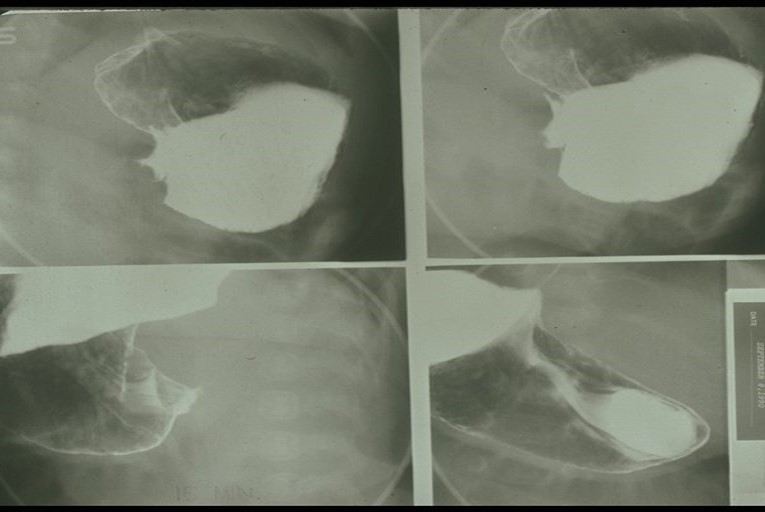

What is the standard imaging study for GERD?

Fluoroscopic barium swallow with UGI.

What are the early radiographic changes in GERD?

Mild esophageal dilation and reduced peristalsis.

What is the late-stage radiographic appearance of GERD?

Smooth, tapered narrowing of distal esophagus due to scarring; Barrett’s esophagus appears stomach-like.

Retrocardiac soft-tissue mass with an air-fluid level.

How do you differentiate the esophagus from the stomach on a barium study?

Esophagus = smooth; stomach = rugal folds.

What is the key landmark to identify in a hiatus hernia?

Diaphragm.